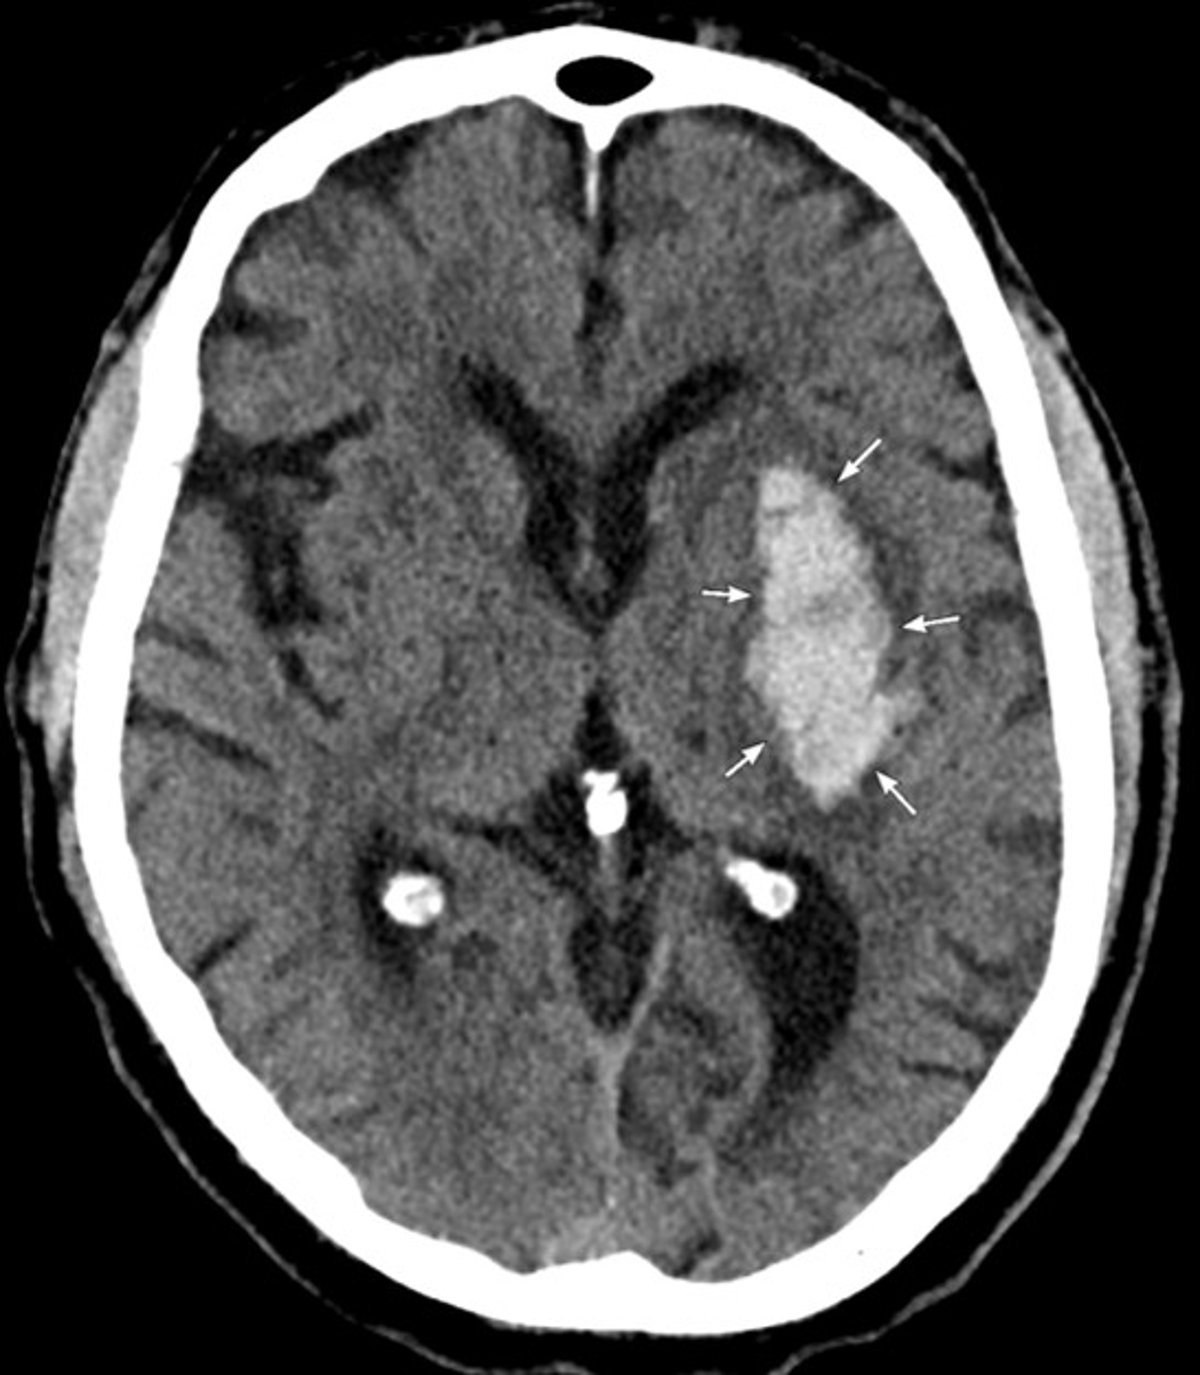

Das CT zeigt eine akute Blutung in den linken Basalganglien, die auf eine hypertensive intrazerebrale Blutung zurückzuführen ist.

Image courtesy of Mustafa Mafraji, MD.